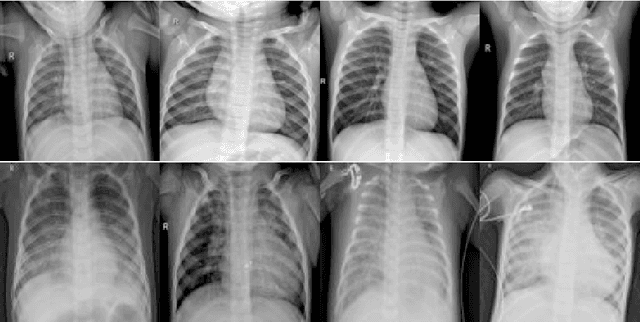

Abstract:Pneumonia is a respiratory infection caused by bacteria, fungi, or viruses. It affects many people, particularly those in developing or underdeveloped nations with high pollution levels, unhygienic living conditions, overcrowding, and insufficient medical infrastructure. Pneumonia can cause pleural effusion, where fluids fill the lungs, leading to respiratory difficulty. Early diagnosis is crucial to ensure effective treatment and increase survival rates. Chest X-ray imaging is the most commonly used method for diagnosing pneumonia. However, visual examination of chest X-rays can be difficult and subjective. In this study, we have developed a computer-aided diagnosis system for automatic pneumonia detection using chest X-ray images. We have used DenseNet-121 and ResNet50 as the backbone for the binary class (pneumonia and normal) and multi-class (bacterial pneumonia, viral pneumonia, and normal) classification tasks, respectively. We have also implemented a channel-specific spatial attention mechanism, called Fuzzy Channel Selective Spatial Attention Module (FCSSAM), to highlight the specific spatial regions of relevant channels while removing the irrelevant channels of the extracted features by the backbone. We evaluated the proposed approach on a publicly available chest X-ray dataset, using binary and multi-class classification setups. Our proposed method achieves accuracy rates of 97.15\% and 79.79\% for the binary and multi-class classification setups, respectively. The results of our proposed method are superior to state-of-the-art (SOTA) methods. The code of the proposed model will be available at: https://github.com/AyushRoy2001/FA-Net.

Abstract:Pneumonia is one of the major reasons for child mortality especially in income-deprived regions of the world. Although it can be detected and treated with very less sophisticated instruments and medication, Pneumonia detection still remains a major concern in developing countries. Computer-aided based diagnosis (CAD) systems can be used in such countries due to their lower operating costs than professional medical experts. In this paper, we propose a CAD system for Pneumonia detection from Chest X-rays, using the concepts of deep learning and a meta-heuristic algorithm. We first extract deep features from the pre-trained ResNet50, fine-tuned on a target Pneumonia dataset. Then, we propose a feature selection technique based on particle swarm optimization (PSO), which is modified using a memory-based adaptation parameter, and enriched by incorporating an altruistic behavior into the agents. We name our feature selection method as adaptive and altruistic PSO (AAPSO). The proposed method successfully eliminates non-informative features obtained from the ResNet50 model, thereby improving the Pneumonia detection ability of the overall framework. Extensive experimentation and thorough analysis on a publicly available Pneumonia dataset establish the superiority of the proposed method over several other frameworks used for Pneumonia detection. Apart from Pneumonia detection, AAPSO is further evaluated on some standard UCI datasets, gene expression datasets for cancer prediction and a COVID-19 prediction dataset. The overall results are satisfactory, thereby confirming the usefulness of AAPSO in dealing with varied real-life problems. The supporting source codes of this work can be found at https://github.com/rishavpramanik/AAPSO